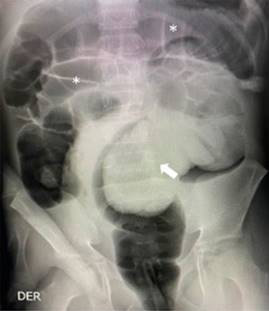

Dos semanas posteriores se realizó colonoscopía total bajo sedación. En el colon sigmoides se encontró un pólipo pediculado gigante de 4 × 2 cm de diámetro, ocupando más de 50% de la luz intestinal (Figura 2). Se procede a enlazar con asa de polipectomía número 20; con coagulación y corte se desprende del pedículo, el cual se recupera y se extrae con canastilla. La paciente no presentó complicaciones durante ni posterior a la polipectomía.

Figura 2: Imagen de colonoscopía: pólipo pediculado de 4 × 3 cm de diámetro (flecha blanca), ocupando más de 50% de la luz intestinal, sin signos de necrosis.